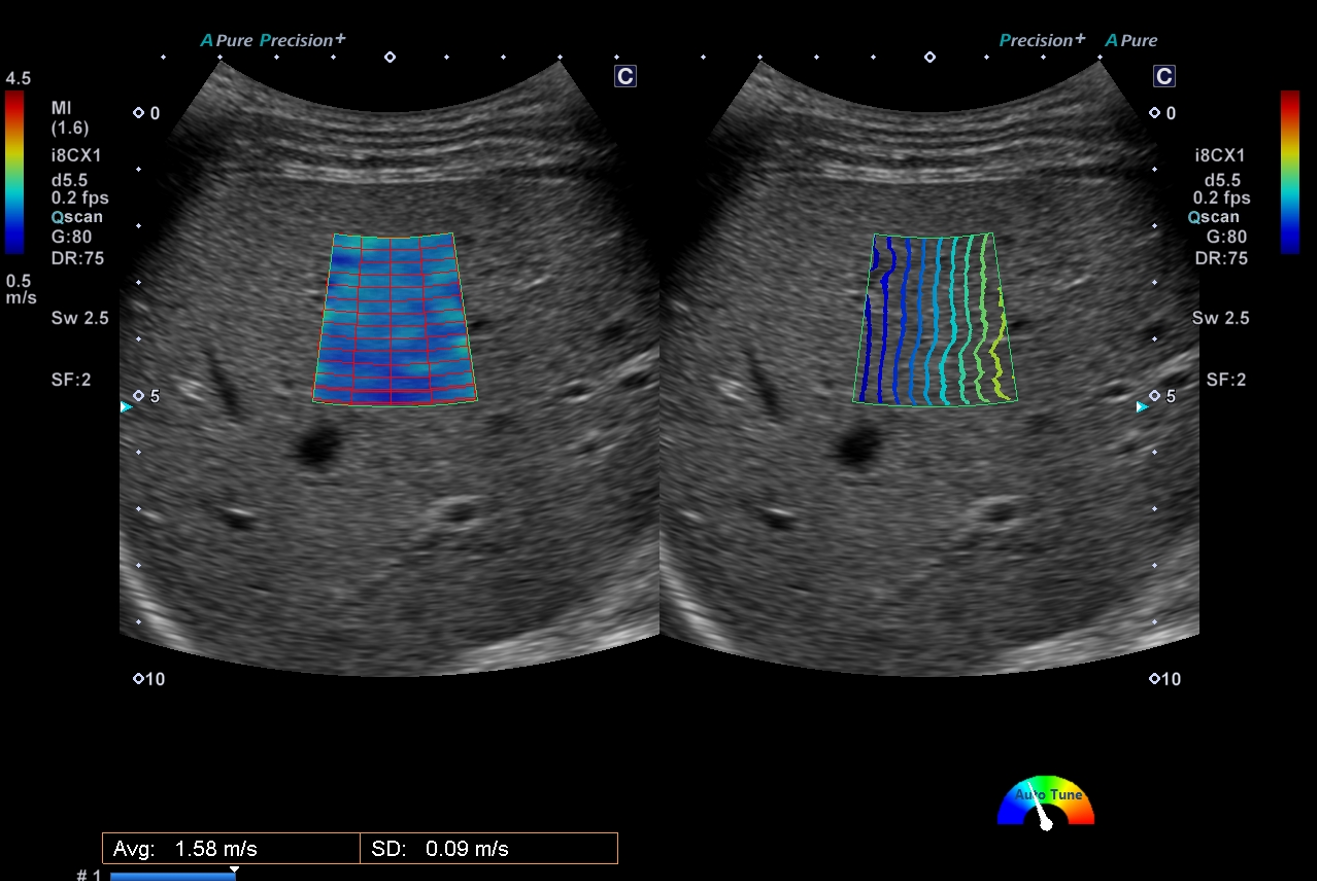

Shear wave Elastography

近年肝臓の硬さをエコーで評価可能となりました。せん断波の伝播速度を測定し、組織の硬さを数値やカラーマップで表示できます。せん断波の伝搬する時間を等高線表示するPropagation表示で、せん断波の伝わり方を視覚的に確認できます。

慢性肝炎や肝硬変の程度の評価が可能となります。